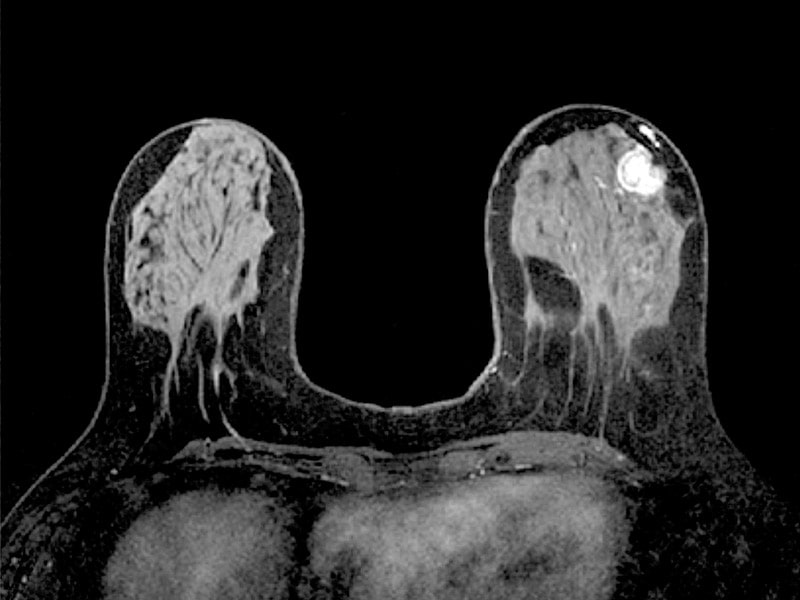

Онкологи в обязательном порядке назначают МРТ молочных желез пациенткам с опухолью в одной груди для того, чтобы выяснить, не поражена ли раком вторая железа. Магнитно-резонансная томография без хирургического вмешательства и просвечивания рентгеном дает детальное изображение внутренних структур молочных желез и кровеносных сосудов, позволяет обнаружить даже маленькие (до 3-5 мм) очаги патологической ткани на самых ранних этапах развития.

МРТ молочных желез может проводиться с контрастированием и без. Контраст (гадолиний – гипоаллергенное окрашивающее вещество) применяется для визуализации сосудистой сети железы. Раковые очаги усиленно кровоснабжаются, что хорошо видно на снимках МРТ.

Во время процедуры больная лежит на животе на подвижной кушетке томографа (для молочных желез в ней предусмотрены специальные отверстия). Длительность процедуры составляет от 30 минут до 1 часа, поэтому женщине необходимо удостовериться, что поза выбрана удобная, и что во время сканирования у нее не возникнет желания пошевелиться.

При проведении МРТ молочной железы с контрастированием через внутривенный катетер медсестра вводит контрастное вещество. Для диагностики рака это обязательная манипуляция. При поступлении контраста в кровь пациентка может испытать холод или небольшой жар, разливающийся по ходу вены.

Заключение с результатом МРТ молочных желез пациентке выдается на руки в течение получаса после процедуры. В описании врач указывает выявленные изменения в груди больной, характер и степень их распространения, локализацию (месторасположение), точные размеры очага, другие параметры и сведения, заключительный диагноз. По данным обследования лечащий врач прогнозирует дальнейшее развитие заболевания и планирует наиболее эффективную схему лечения.

При МРТ молочных желез при подозрении на рак используется болюсное динамическое контрастирование. Контрастное вещество впрыскивается в определённый момент времени, и это позволяет найти зоны повышенного кровоснабжения. Чем злокачественнее образование, тем оно сильнее кровоснабжается. Задача врача — определить эти места и оценить степень накопления контраста. По этим данным он сможет ответить на вопрос, носит ли опухоль доброкачественный или злокачественный характер.